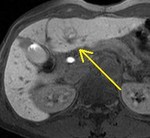

[画像メモ]デスモイドについて 2011-03-08

[詳細は「タカ派の画像診断医」へ)